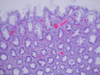

Classify this endometrial hyperplasia

Simple hyperplasia without atypia

Classify this endometrial hyperplasia

Complex without atypia

Classify this endometrial hyperplasia

complex atypical